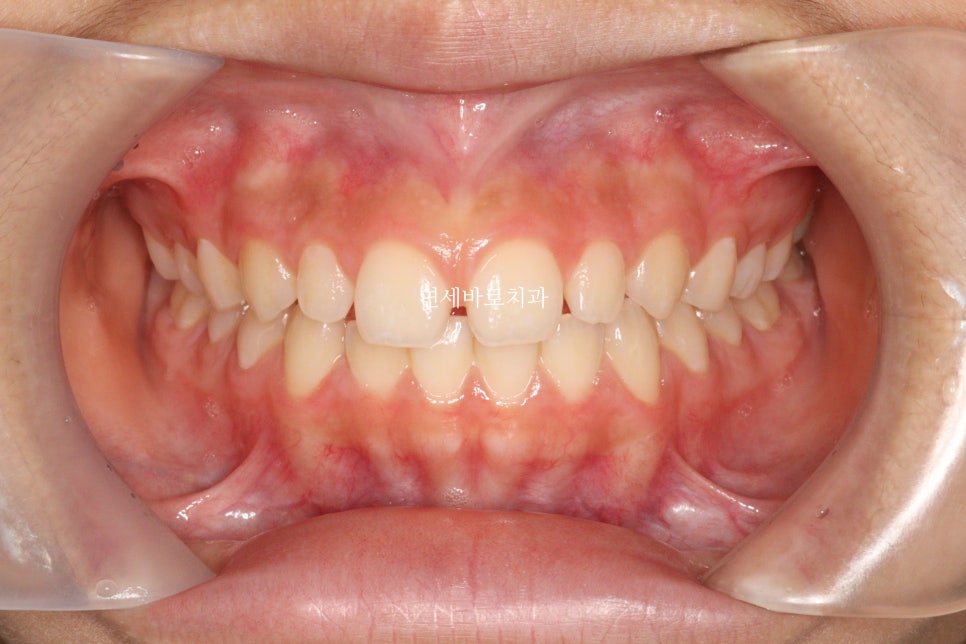

그래서 20세정도까지는 임시로 채워넣거나. 그냥 벌어진상태로 지내야 합니다.

최종적으로 아이는 레진으로 임시로 공간을 매꾸기로 했습니다.

임시라지만 오랜시간 사용해도 됩니다.

왜소치(치아가 작은 경우)와 앞니 형태가 항아리 모양인 경우 교정치료 후에도 치아 사이에 공간이 남을 수 있습니다.

중학생이 라미네이트 치료를 받을 수 있나요?

중학생과 같은 성장기에는 잇몸의 성장이 남아있어 라미네이트 치료 시 성인이 되어서 경계부분이 맞지 않을 수 있어 20세 정도까지는 임시 레진으로 공간을 채우는 것이 일반적입니다.